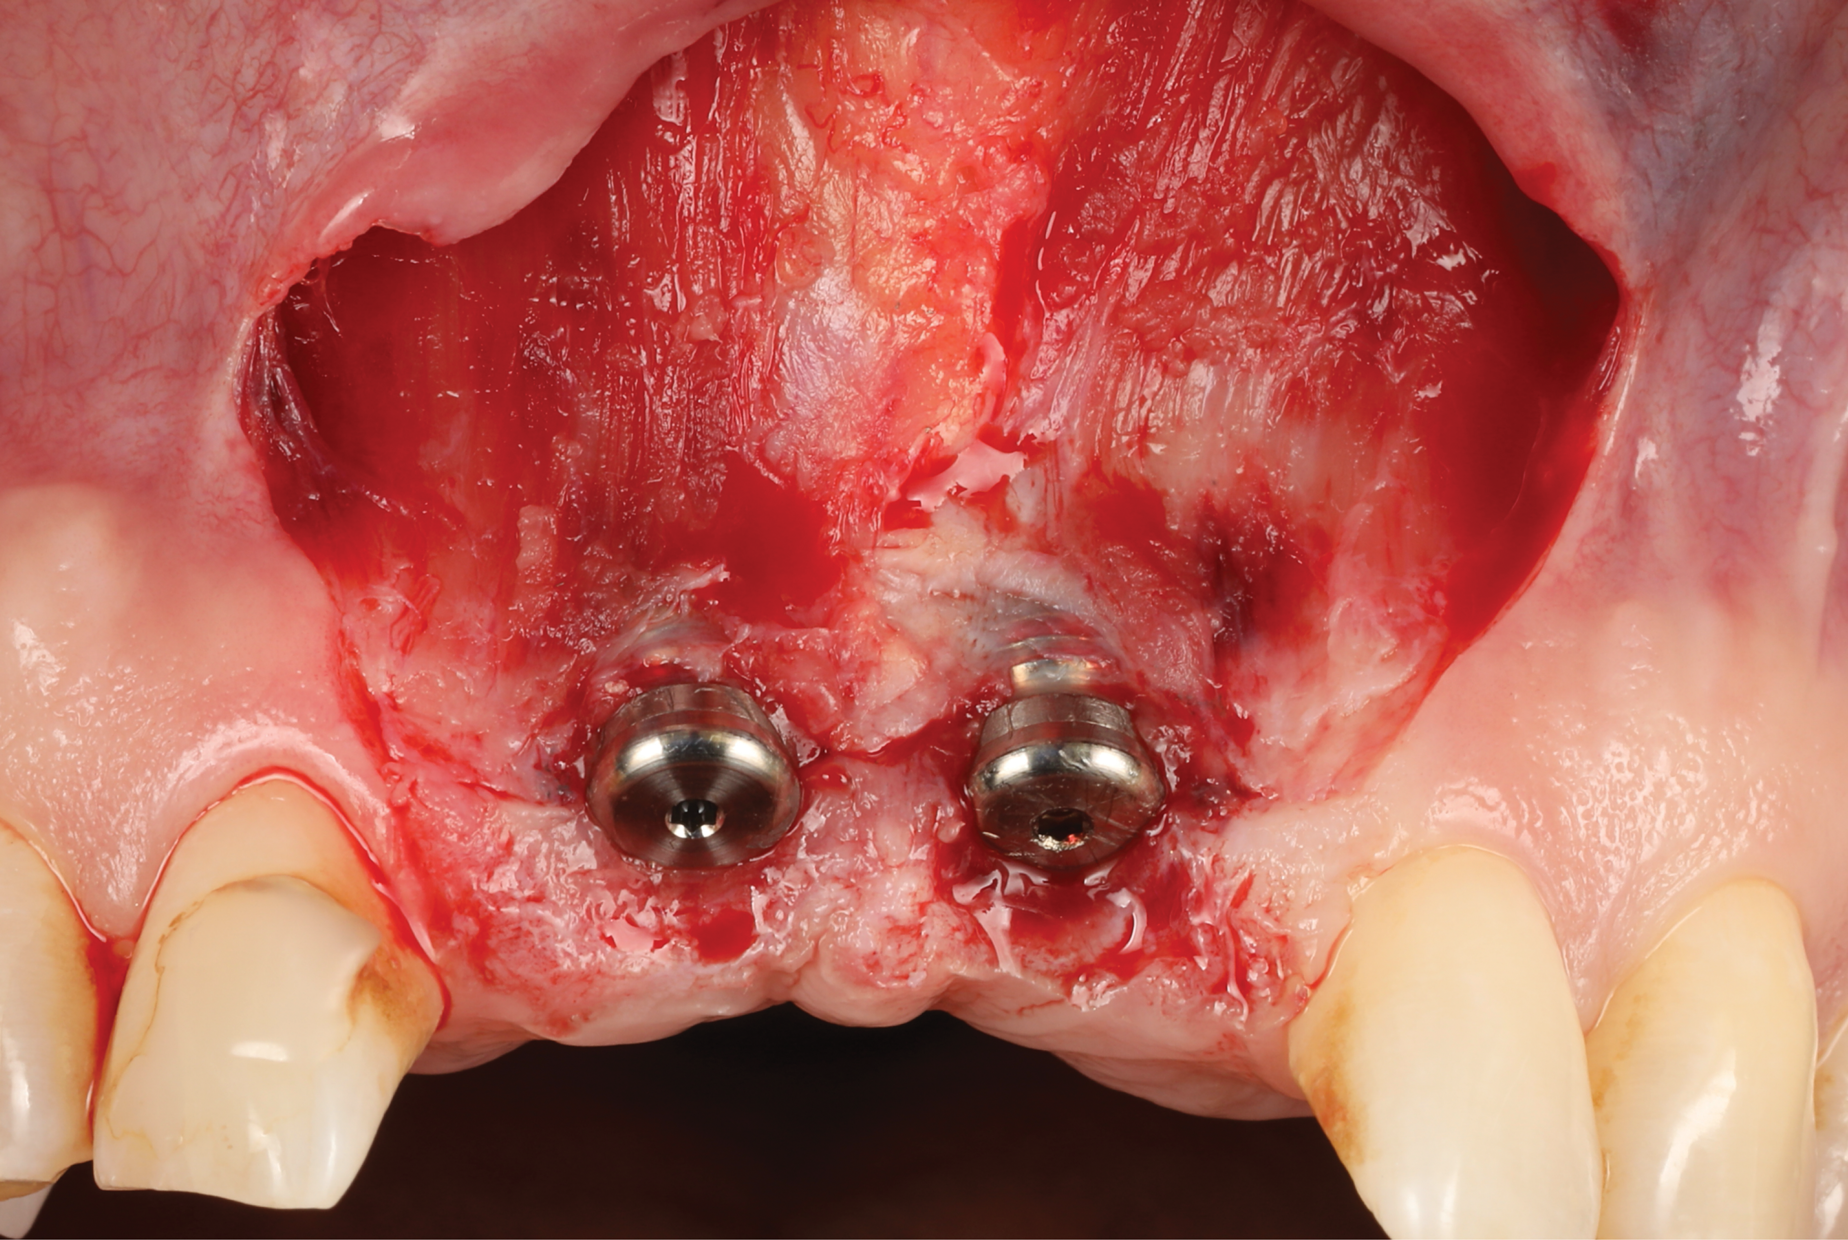

Oral hygiene instructions were reviewed with the patient and reinforced 6 weeks before the surgical visit. At the surgical appointment, the implant-supported crowns and abutments were removed, and two cover screws were inserted. A split-thickness trapezoidal-shape CAF was performed (Figure 3). The two slightly divergent beveled oblique incisions were placed between the implants and lateral incisors. A split-thickness flap was elevated, with meticulous care taken to maintain a layer of connective tissue adherent to the implant surface. Maintaining this layer of connective tissue on the implant body lacking buccal bone is an important step that differentiates flap elevation on healthy implants with PSTDs from implants with peri-implantitis (Figure 4).

After this elevation, the flap was released with a deep incision parallel to the bone and then with a superficial incision with the blade parallel to the external mucosal surface, until it was able to passively reach a position approximately 2 mm coronal to the ideal final level of the soft-tissue margin. The anatomical papillae between the implants and lateral incisors and the inter-incisive papilla were de-epithelialized with a microblade, not only on the buccal aspect but also in the occlusal region to enhance the vascular bed for the flap.

Fig 3. Coronally advanced flap after removal of the crowns for soft-tissue augmentation.

Figure 3

Fig 4. Split-thickness flap elevation.

Figure 4